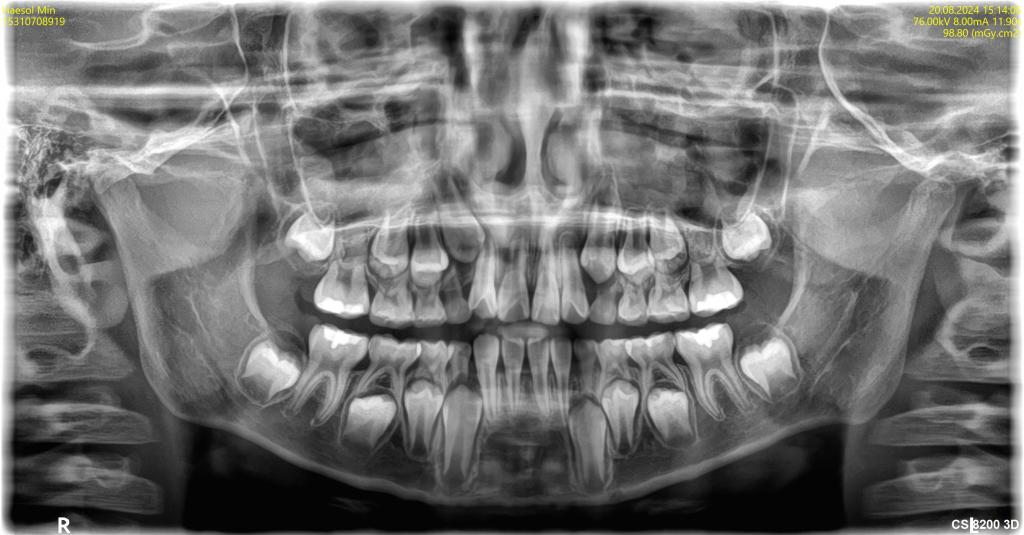

치아뿌리 움직임 봐주세요ㅜㅜ

선생님 안녕하세요~ 아이 교정 마무리 단계에서 x-ray 촬영을 하였는데 하악 왼쪽 송곳니와 상악 오른쪽 송곳니 뿌리 부분이 비스듬히 쓰러져 있더라구요 혹시 교합은 안건드리고 뿌리 부분만 바로 세우는 이동이 가...

교정마무리 한번만 봐주세요~

안녕하세요 선생님~^^ 교정을 하면서 선생님께 도움을 많이 받았습니다. 감사합니다 아이 교정이 이제 마무리가 다가 옵니다 과개교합과 왼쪽 2대구치 상.하악 가위교합으로 비발치 교정을 하였습니다 아이 치아다 보...

치아 뿌리끝이 갈고리처럼 휘었어요

(사진펑할께요~) 선생님 안녕하세요~^^ 궁금증에 대해 친절한 답변을 주셔서 감사합니다^^ 아이가 교정중에 있다보니 궁금중이 많은 엄마입니다. 파노라마 사진을 찍고보니 치아 뿌리 끝쪽이 90도로 휘어져 있어요ㅜ...